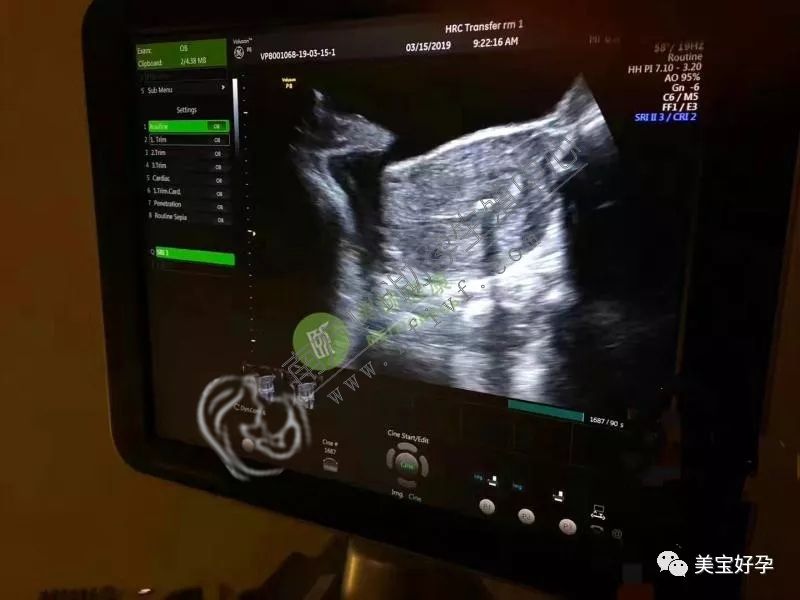

周二,为苏州张氏夫妇助孕的爱心妈咪来到诊所进行了移植手术,这是一位漂亮的美女姐,从答应帮助张先生一家做第三方辅助助孕以来她一直很兴奋,这是她第一次帮助别人,一种神圣的孕产使命感驱动着她用非常认真的心态对待此次移植手术。

虽然整个过程仅有短短的五分钟,但她已经为此调理了很长一段时间的身体,要以最好的状态来迎接这个小天使的到来。